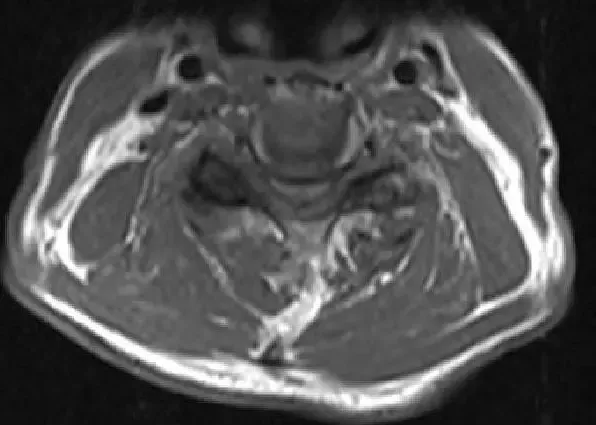

Imagen de resonancia magnética T2 Corte axial que muestra estenosis y compresión severa de la médula espinal en C3-4